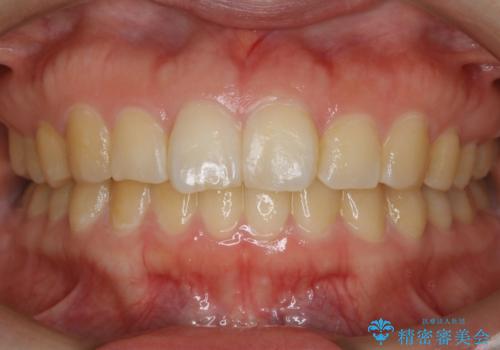

【非抜歯】ガタつきと歯軸を正して長持ちする歯へ

- 歯のガタつきと噛み合わせの改善を主訴に来院されました。

非抜歯で、少量の奥歯の移動と歯列の拡大・IPRを駆使して主訴を改善するための治療計画を立案しました。